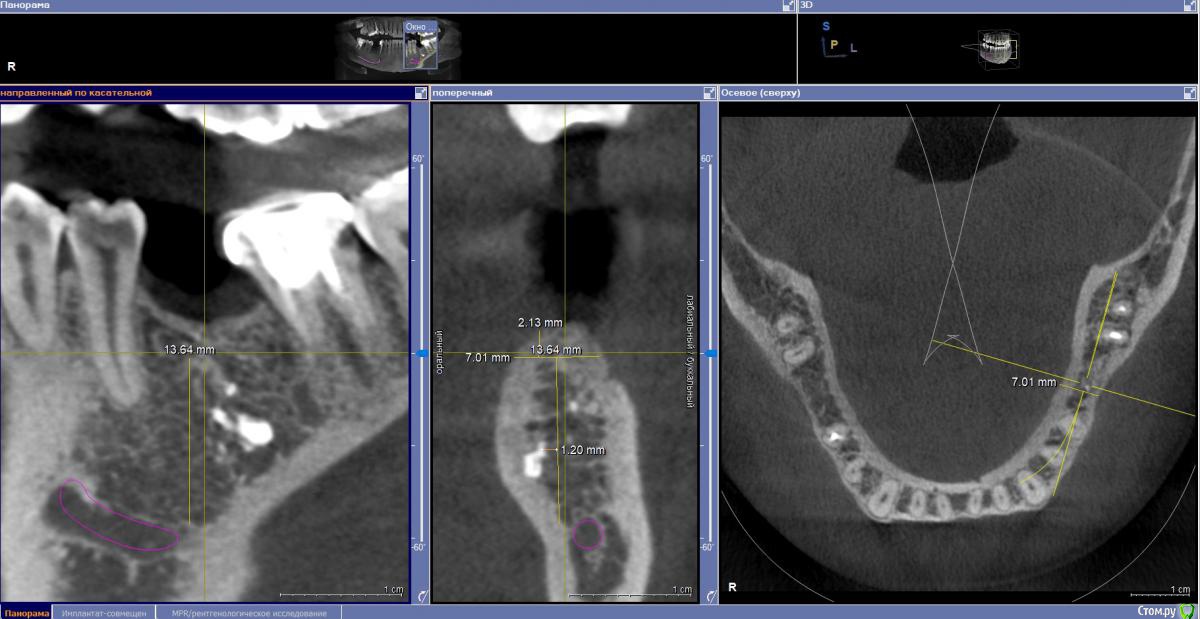

zumanok Опубликовано 19 января, 2020 Поделиться Опубликовано 19 января, 2020 Здравствуйте доктора. На этой неделе появилось два клинических случая. В обоих случая проекция будущих имплантатов располагается в области пломбировочного материала. На форуме есть подобные темы, но в данном случае прямой контакт с материалом. Стоит ли пытаться полностью убирать материал?Делать отдельный доступ? Как вариант сначала попробовать просверлиться на глубину материала и твердосплавным шариком 1000 об с максим. охлаждением поработать по стенкам ложа. Дополнительно делать РГ контроль.Как бы вы поступили в данных случаях? Ссылка на комментарий

dok1 Опубликовано 20 января, 2020 Поделиться Опубликовано 20 января, 2020 От объема, капсулы. Чуйки , в конце концов . Можно поиграть положением импланта и в первом и во втором случаях. Обойти дегко и там и там 2 Ссылка на комментарий

masterdent Опубликовано 20 января, 2020 Поделиться Опубликовано 20 января, 2020 можно обойти, но лучше рентгенкотроль по готовности шахты, тогда ясно будет, ушел материал на фрезе или нет Ссылка на комментарий

zumanok Опубликовано 21 января, 2020 Автор Поделиться Опубликовано 21 января, 2020 От объема, капсулы. Чуйки , в конце концов . Можно поиграть положением импланта и в первом и во втором случаях. Обойти легко и там и там Во втором случае тоже думаю что можно обойти, но вот в первом случае по мне только через материал.Фрезой можно выбрать. 2-х милиметровой. Обычно там рыхлее кость.Спасибо попробую, а как на счет твердосплавного бора? Поидее им проще работать будет и лишнего особо не уберешь. Ссылка на комментарий